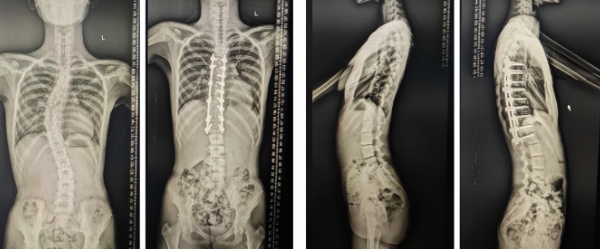

本次邱勇院士除将常规进行看诊活动外,还将为一名患有“脊柱半椎体畸形”小患者进行矫形手术。胸腰椎半椎体畸形,是儿童先天性脊柱畸形中较为复杂的一种类型——因胚胎发育异常,患儿脊柱某一节段仅形成了“半个椎体”的结构,导致脊柱受力失衡,随生长发育逐渐出现侧弯、后凸畸形,严重时会压迫胸腔、腹腔脏器,影响呼吸功能、神经功能,甚至阻碍孩子的生长发育。 “半椎体畸形若不及时干预,侧弯角度将逐年增加,等到孩子青春期发育高峰,病情会加速进展。这类畸形无法通过支具、康复训练逆转,手术是唯一能真正矫正脊柱结构、阻断病情进展的方式,但手术难度极高——需要精准切除半椎体,再通过内固定重建脊柱稳定性,既要保证矫正效果,又要最大程度保护脊髓神经,避免术后并发症。”

本次即将接受手术的患儿小宇(化名),今年10岁,半年前被查出胸段脊柱半椎体畸形,当地医生说手术难度大,建议去南京鼓楼医院找邱勇院士手术。得知邱勇院士定期赴青进行看诊手术工作,一家人连夜退掉去南京的火车票,赶往青岛市海慈中医医疗集团预约挂号并就诊。通过邱勇院士的悉心检查,确定小宇可以采用最经典的半椎体切除融合内固定的治疗方式,并决定就在集团脊柱外科进行手术。“终于不用带孩子跑南京了,在家门口就能让最顶尖的专家做手术,心里踏实多了。”患者的父亲欣慰地说。

脊柱矫形手术因高创伤性、高出血量、高操作难度,被誉为“脊柱外科领域的珠穆朗玛峰”,而半椎体畸形矫形手术,更是其中的“硬骨头”——需要在脊髓神经间隙中切除异常椎体,再植入螺钉、钛棒重建脊柱序列,任何微小失误都可能导致神经损伤、瘫痪等严重并发症。为确保小宇手术万无一失,邱勇院士团队已提前启动“全流程精准准备”。

早在一周前,团队联合影像科,获取了小宇的全脊柱CT、MRI数据,并用3D打印技术制作出1:1的脊柱实体模型。模型上清晰标注了半椎体的位置、大小,以及需要植入螺钉的椎体节段、椎弓根螺钉的欲置入角度——这相当于为手术团队绘制了一份“精准导航图”。“很多半椎体畸形的患者,相邻椎体还存在解剖变异,螺钉置入位置必须精确到1毫米。”邱勇院士解释,团队会通过术前模拟手术,反复调整螺钉置入路径,避免术中损伤脊髓或血管。手术中还将开启术中3D导航系统,该系统可以实时显示椎体位置、螺钉深度,确保每一枚螺钉都精准植入安全区域。 同时,集团脊柱外科杨希重主任团队联合麻醉科以及围手术期护理小组制定计划:麻醉科将备好“术中唤醒试验”设备——手术中会让患儿在清醒状态下活动脚趾,并通过脊髓电生理仪的监测,时刻了解脊髓功能;同时安排专人提前测量,预先准备术后的支具。护理团队制定了术后康复计划,包括腰背肌力量训练、呼吸功能锻炼等,确保术后快速恢复。